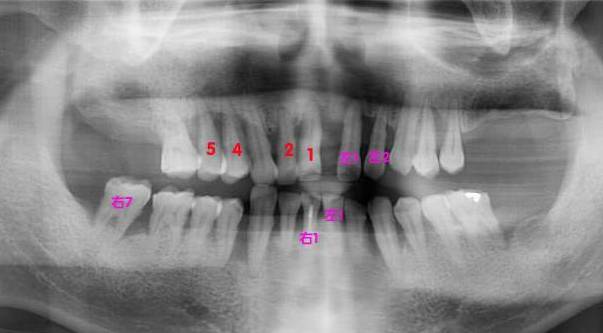

【byb.cn 大道至簡】2015年1月10日,我同時拔掉了4顆牙,即右上1、2、4、5顆牙,保留了3、6;與此同時,我還將在1月14日,繼續(xù)拔4顆牙,即左上1、2,左下1、右下1和右下7。換言之,在4天之內,我要拔掉9顆牙。

這次拔完牙之后,我上面還留有5顆,下面還留有9顆,共計14顆真牙,其余的牙,將被活動義齒所取代。

紅色的,是在1月10日拔掉的牙,粉色的,是即將在1月14日拔掉的牙